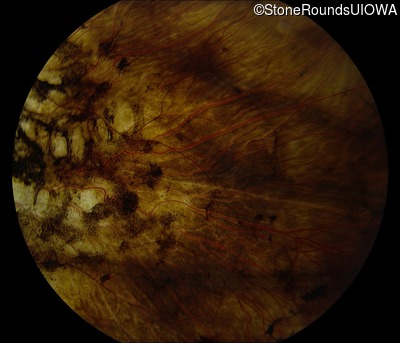

Fundus Photography - Right - 5/200 sc

Fundus Photography - Left - Hand Motion sc

Fundus Montage - Right - 5/200 sc

Fundus Montage - Left - Hand Motion sc

Infrared Fundus Photograph - Right - 5/200 sc

Infrared Fundus Photograph - Left - Hand Motion sc